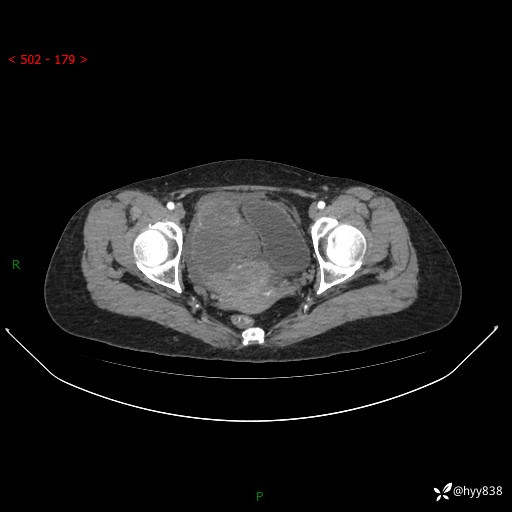

腹盆CT平扫

增强